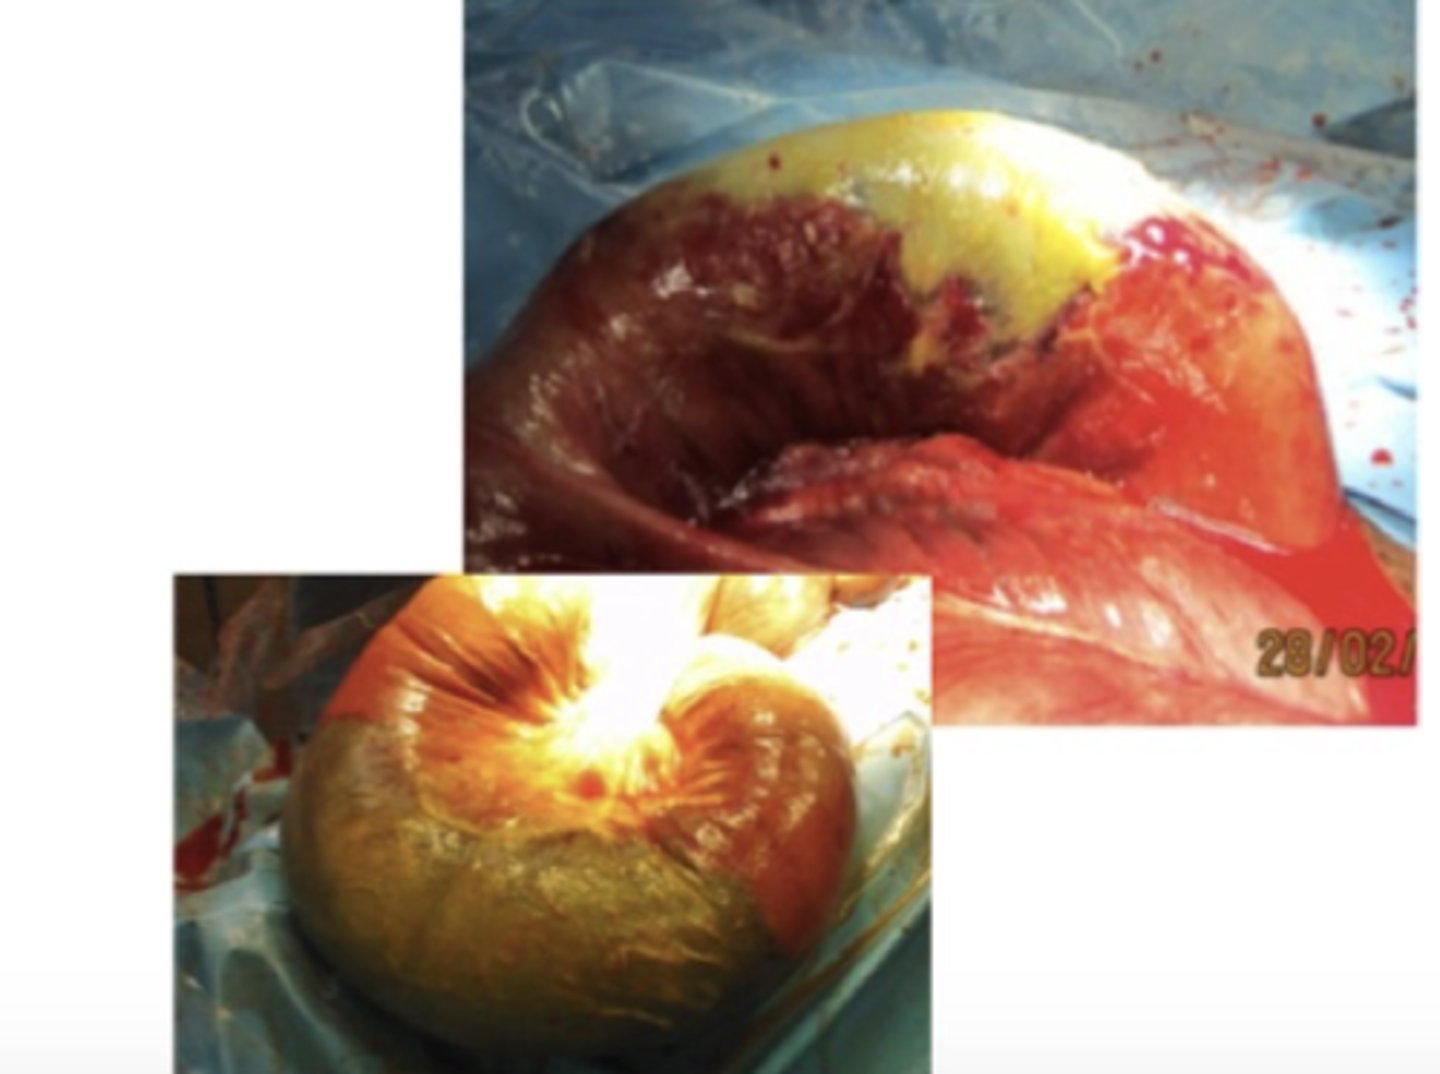

Non-strangulerende intestinal nekrose

En hest på 6 år har haft mild kolik og feber i nogle dage. Ved indlæggelsen på hospitalet diagnosticeres hesten med peritonitis og der foretages en eksplorativ laparotomi. Hvordan vil du karakterisere denne læsion i flexura pelvina?

- Strangulerende intestinal nekrose

- Non-strangulerende intestinal nekrose

- Non-strangulerende intestinal inflammation

- Strangulerende intestinal ischæmi

Trombo-embolisk infarkt

Ved en eksplorativ laparotomi på en hest med kolik og peritonitis, findes denne læsion på Flexura Pelvina. Hvad er den mest sandsynlige årsag til dette?

- Neoplasi

- Obstruktion

- Trombo-embolisk infarkt

- Colitis